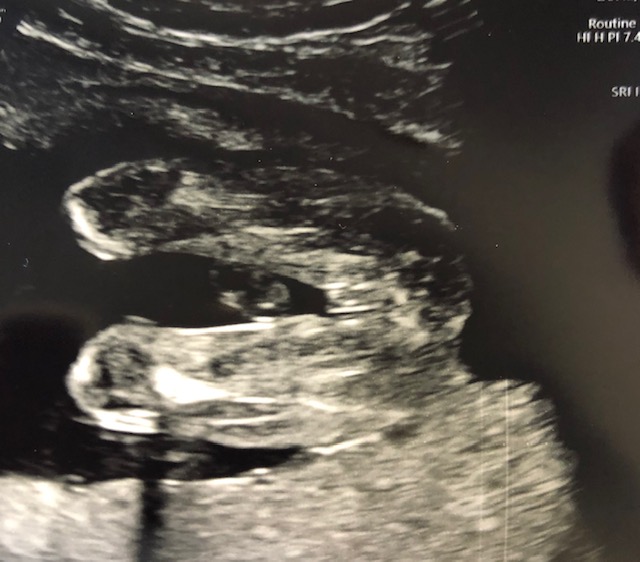

Here's our latest scan. None of my boys have looked like this, but thoughts on gender?

Girl. A few inches out is a piece of cord but that's a pretty clear shot of labia. The "three white lines" sign. :) Congrats!

Yes, I see that little something sticking out too, but it's totally unfamiliar, haha! Thank you, ladies. I won't officially OFFICIALLY know until the baby comes out, but I hope these signs stay true. I'm in shock. <3

We can be wrong though. REmember we only see what the tech captures on the screen and they can zoom in on some parts and obscure others, especially if they think you didn't want to know gender.

Still, I'll be pretty shocked if that's a boy. :)